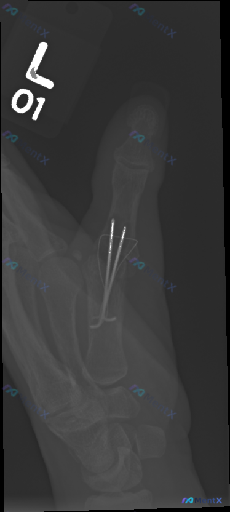

整理了一份左手拇指术后复查的影像资料,先看第一印象: - 左手拇指斜位X光,第一掌指关节(MCP)有两枚克氏针固定,穿过近节指骨基底到第一掌骨头 - 骨折线处可见骨痂形成,骨皮质尚连续,没看到明显骨质破坏或脱位 - 周围软组织没报明显弥漫性肿胀,籽骨位置也正常 报告首先提示是“术后修复状态”,但这份...

整理一份右手指部的X光正位影像资料,最醒目的是两枚金属克氏针——一枚从第3掌骨基底部穿到近节指骨,另一枚对应第4指,两根都跨了掌指关节,近端还在皮下留了钩状弯曲。 骨皮质能看到不连续或者陈旧性骨折线的痕迹,目前没看到明显的溶骨、广泛骨膜反应,植入物周围也没有透亮带。 问题来了:如果问“这张影像里有什...